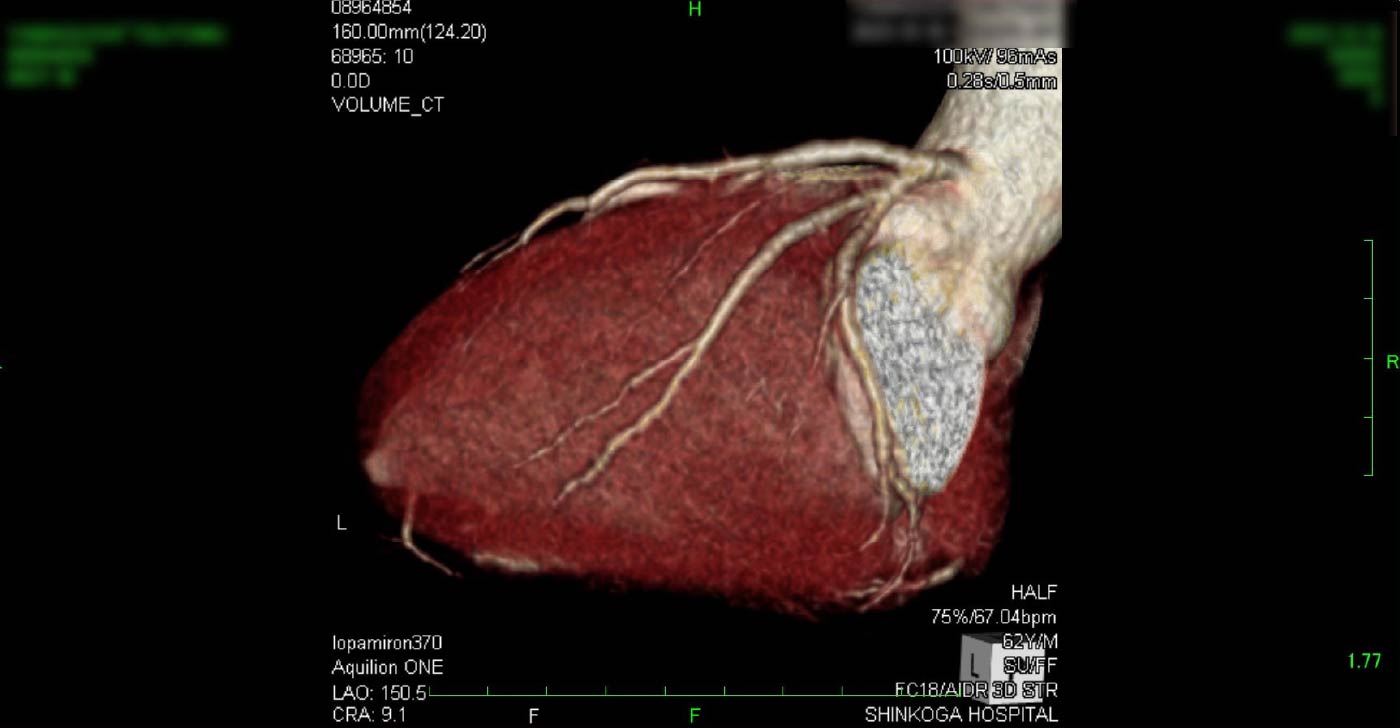

進行期 造影心臓CT 重症心筋虚血症例

冠動脈CT

狭心症を安全に診断あるいは除外する!

連携施設の新古賀病院で速やかに実行可能です。

冠動脈CT 冠動脈CT 冠動脈CT 冠動脈CT 冠動脈CT 冠動脈CT 冠動脈CT 冠動脈CT 冠動脈CT 冠動脈CT 冠動脈CT 冠動脈CT 冠動脈CT 冠動脈CT